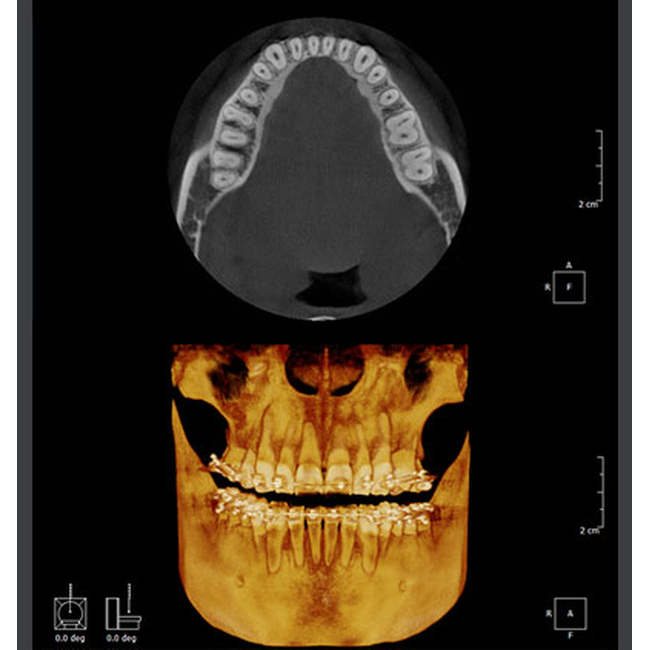

Мощное и практичное программное обеспечение для анализа трёхмерных изображений